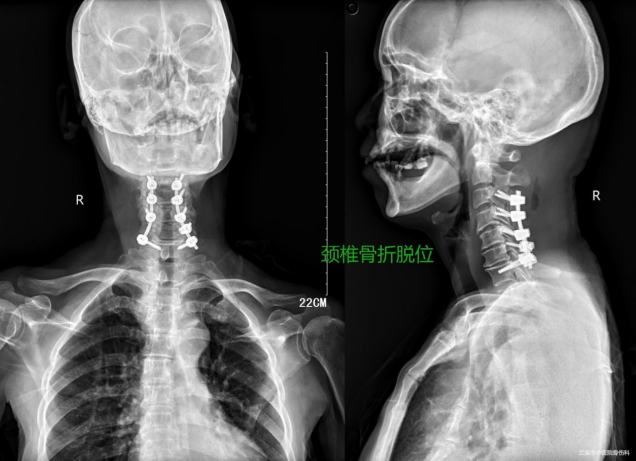

脊柱领域

颈椎增生明显,为患者行颈椎单开门减压术